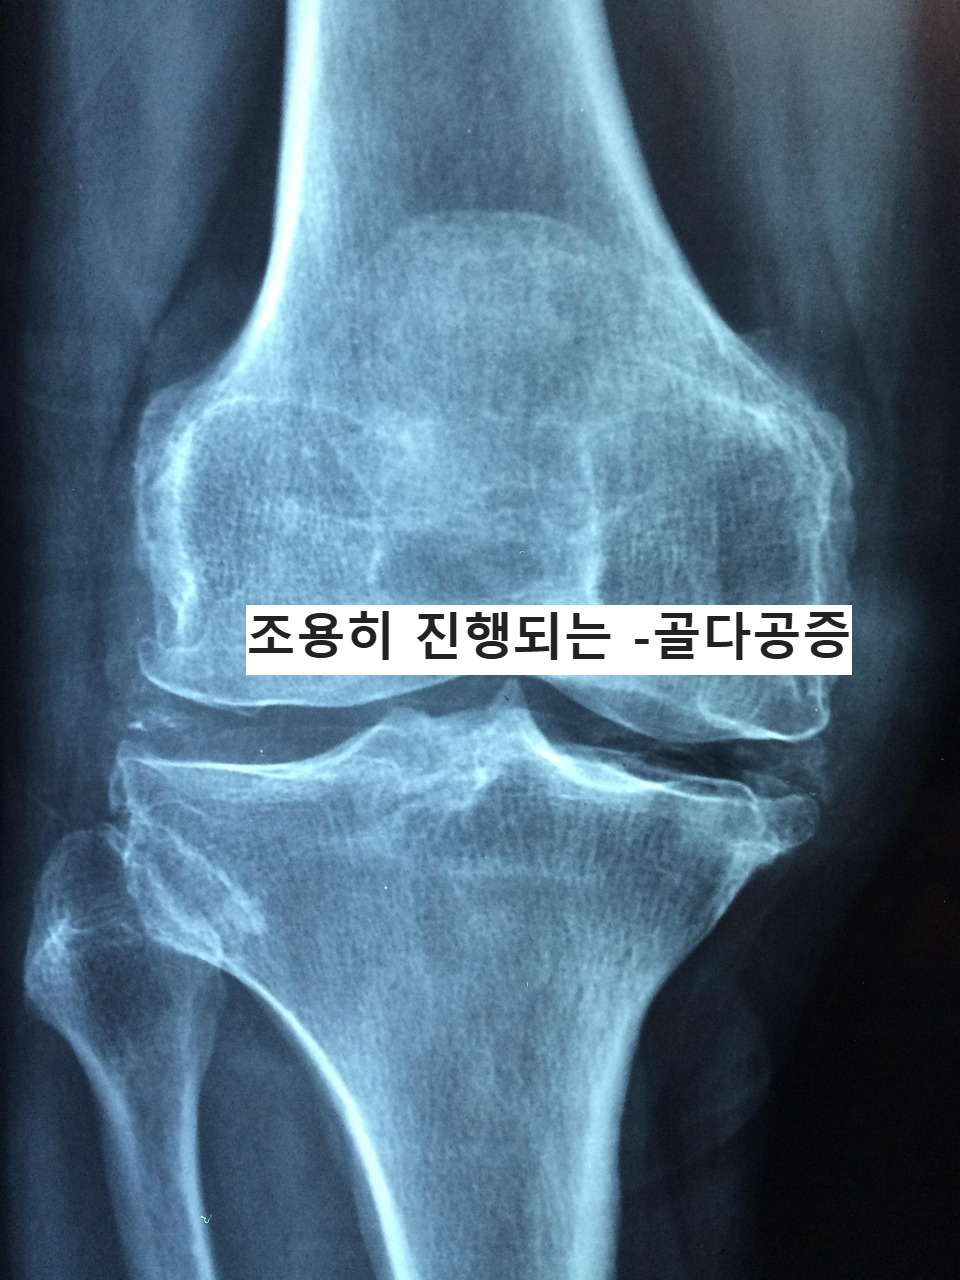

골다공증, 조용히 진행되지만 결코 가볍지 않은 뼈의 변화

골다공증이란 무엇일까

골다공증은 말 그대로

뼈의 밀도가 낮아지고 구조가 약해지는 상태를 의미한다.

겉보기에는 멀쩡해 보여도

현미경으로 보면 뼈 속이

스펀지처럼 듬성듬성 비어 있다.